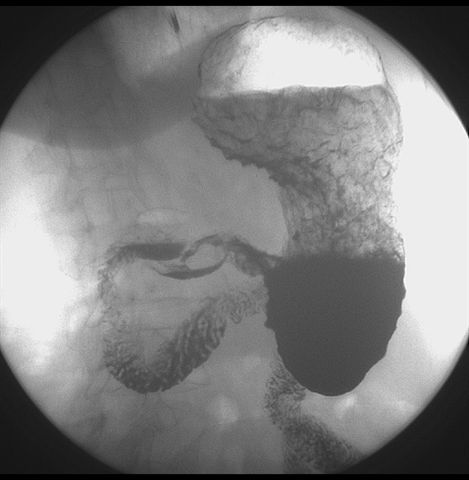

标题: X6872:F,69y,胃部不适。

胃窦至幽门段胃壁僵硬,扩张受限,局部纠集粘破坏,呈杵状。提示溃疡癌变可能性大。

胃窦癌可能性大,建议胃镜活检。钡剂太稀,吃的有点多。

支持考虑胃窦癌可能,胃内滞留液太多,胃窦部僵硬。

瀑布型胃,胃粘膜那是一个乱,窦部充盈不好,第16幅窦部粘膜反倒又很顺,先定个胃炎胃窦炎胃窦癌待排之类,建议进一步作胃镜检查。

胃窦部见钡池影,局部粘膜紊乱,纠集呈杵状改变,胃壁扩张受限,胃窦癌可能性大,建议胃镜检查.

胃窦部管腔扩张度较差,形态略有改变,胃窦粘膜显示欠佳,胃窦部占位可能性大,结合胃镜活检。

胃窦部狭窄、稍僵硬,考虑胃窦癌?建议胃镜检查。

北京肿瘤医院胃镜诊断皮革胃。